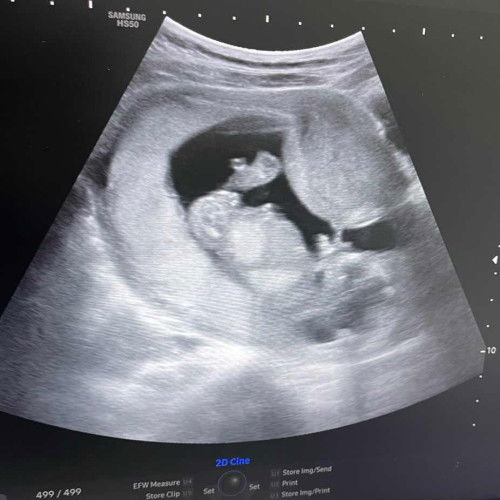

ภาพอัลต้าซาว

ช่วยดูหน่อยค่ะว่าตรงไหนคือส่วนไหน น้องผู้ชายค่ะ